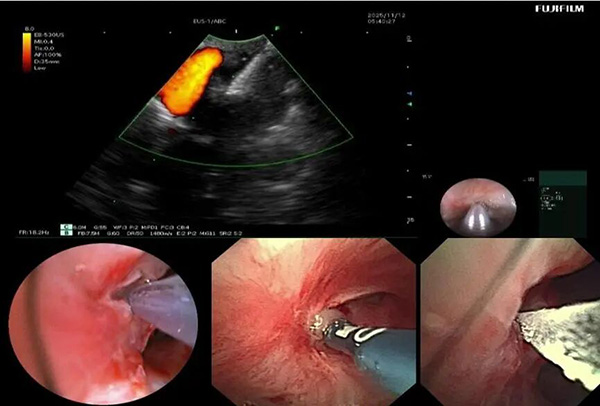

入院后,呼吸与危重症医学科介入团队对患者病情进行全面评估。完善胸部增强CT提示:右肺上叶大片状实变并坏死,支气管完全闭塞。由于前期单纯口服抗真菌药物效果不佳,因此联合气管镜下介入治疗势在必行。经过认真评判,团队制定了详细的气管镜下介入诊疗计划。治疗过程包括:超声支气管镜引导下精准穿刺,高频电刀微创开窗建立引流通道;钳夹清除远端大量坏死组织;局部灌注抗真菌药物以提高病灶药物浓度;结合球囊扩张与超细冷冻冻融治疗,扩大引流窗口;并多次行镜下冲洗,彻底清除分泌物与坏死物。

▲支气管镜下多种内镜器械联合使用

▲呼吸介入团队进行镜下治疗